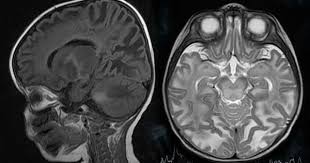

Canavan disease is usually diagnosed within the first 3 to 6 months of life when babies do not meet their early motor milestones. In type 2 Gaucher disease acute infantile neuropathic Gaucher disease symptoms including seizures spasticity limb rigidity are apparent by 3 months of ageInfants may have extensive and progressive brain brain damage. Canavan disease is a gene-linked neurological disorder in which the brain degenerates into spongy tissue riddled with microscopic fluid-filled spaces.

Canavan Disease In A 6 Month Old Infant Who Presented With Hypotonia Download Scientific Diagram